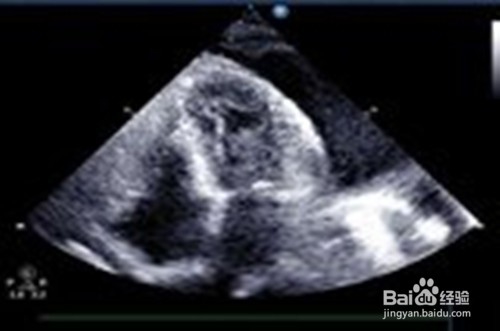

6、B超检查 如积液在左侧,则心脏被遮掩。大量积液时,可见气管和心脏向一侧移位。病区呈大片模糊的阴影。B超能准确诊断和定位胸膜炎病症位置。